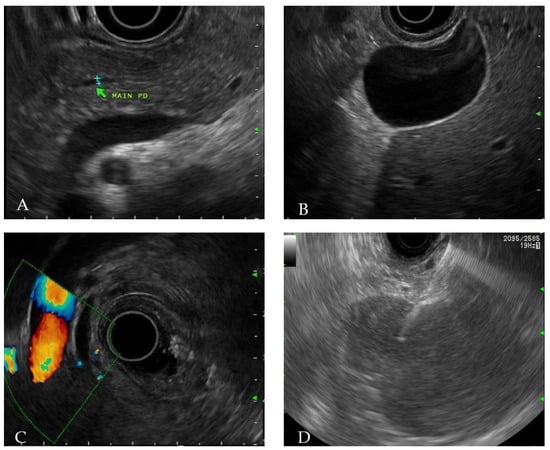

The patient did not exhibit disseminated lymphoma throughout his entire body. After confirming no additional abnormal findings, chemotherapy using the same regimens, Dexamethasone, methotrexate, ifosfamide, L-asparaginase, and etoposide (SMILE), was started. On Day 8 of chemotherapy, L-asparaginase (6000 IU/m2) was administrated and he complained of sudden onset epigastric pain and tenderness after 2 days. He was hemodynamically stable at the time, and his blood test results were mostly normal with the following values: white blood cell 4400/mm3 (neutrophil 67.2%, lymphocyte 23.8%), hemoglobin 12.8 g/dL, platelet 165,000/uL, total bilirubin 0.7 mg/dL, aspartate transaminase 33 IU/L, alanine transaminase 24 IU/L, alkaline phosphatase 63 IU/L, gamma-glutamyl transferase 14 IU/L, triglyceride 123 mg/dL, calcium 8.2 mg/dL, and IgG4 707 mg/L. However, he had elevated levels of amylase (683 U/L) and lipase (1437 U/L), which were three times higher than the normal value. Under abdominal CT (2 days before EUS-FNB), diffuse enlargement of the pancreas was observed compared to the pre-chemotherapy CT (Figure 1B), although neither abnormal mass at pancreas parenchyma nor fluid collection at the peripancreatic area was observed (Figure 2A–C).

Figure 2.

Pancreas finding during chemotherapy. Diffuse pancreas swelling was observed: (A) non-enhanced phase (B) arterial enhanced phase (C) venous enhanced phase.